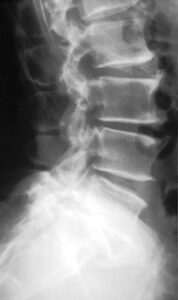

Kan in zowat elk gewricht optreden: wervelkolom (rug, nek), heupen, knieën, voeten, schouders, vingers, zelfs kaakgewrichten. Gewrichten met veel belasting, zoals knieën en lage rug, zijn extra gevoelig.